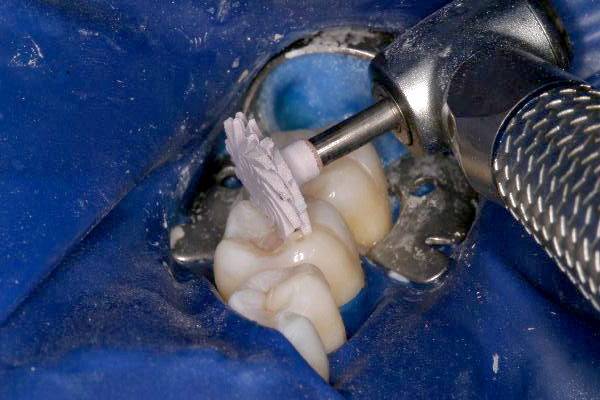

Click on an image below to enlarge & view caption.

Dentistry and photography courtesy of Dr. Robert Margeas.